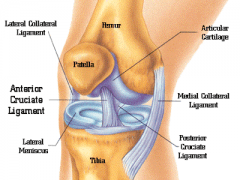

什么是〝半月板〞软骨?